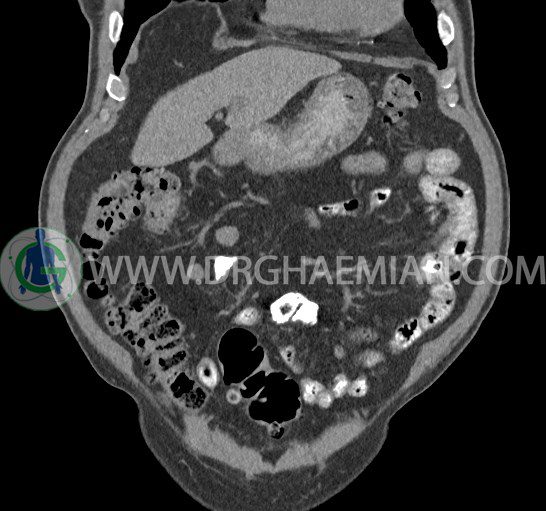

سی تی اسکن لگن یکی از روش های تصویربرداری با سی تی اسکن است. این روش با استفاده از تشعشعات تصاویر عرضی از ناحیه شکمی ایجاد میکند. در این کیس ديورتيكولوزيس، کیست های کورتیکال در هر دو کلیه، لنفادنوپاتی، کلسیفیکاسیون دیواره آئورت و شریان ایلیاک، تغییرات DJD ناحیه توراکولومبار و پروستات بزرگتر از عادی دیده می شود.

در سي تي اسکن اسپيرال شکم و لگن با و بدون کنتراست خوراکی و وريدی (مولتي ديدکتور 16 با مقاطع ظريف و بازسازي هاي ساژيتال و کرونال):

– کيست هاي کورتيکال ساده به قطر 5 mm تا 50 mm در کليه راست و به قطر 5mm تا 55 mm در کليه چپ

– توده ايزودنس به ابعاد mm 17 x 28 در پره ائورت مجاور قسمت تحتاني D3 دئودنوم مطرح کننده لنفادنوپاتي و با احتمال کمتر آنوريسم ترومبوزه (نيازمند مطابقت سونولوژيک)

– کلسيفيکاسيون ديواره آئورت و شريان ها ايلياک همراه با نشانه هاي ترومبوز مورال در بيفورکاسيون ائورت با امتداد به پروگزيمال هاي شريان هاي ايلياک

– ديورتيكولوزيس در کولون نزولي وسيگموئيد

لنفادنوپاتي به ابعاد mm 22 x 25 مجاور شريان ايلياک خارجي چپ و به ابعاد mm 17 x 28 مجاور شريان ايلياک خارجي راست

– تغييرات DJD در ناحيه توراکولومبار و

– پروستات به ابعاد mm 45 x 54، بزرگ تر از نرمال

مشهود است.